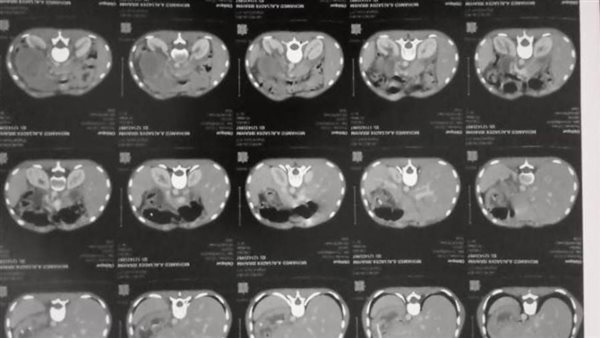

أشاد اللواء هشام آمنة محافظ البحيرة بجهود ونجاح الفريق الطبي بقسم الجراحة العامة وجراحة المناظير بمستشفى شبراخيت المركزي في استئصال جزء من الأمعاء الدقيقة وإعادة التوصيل لشاب في العقد الثالث من عمره يعاني من انسداد في الامعاء متكرر نتيجة متلازمة بوتز جيغرز.